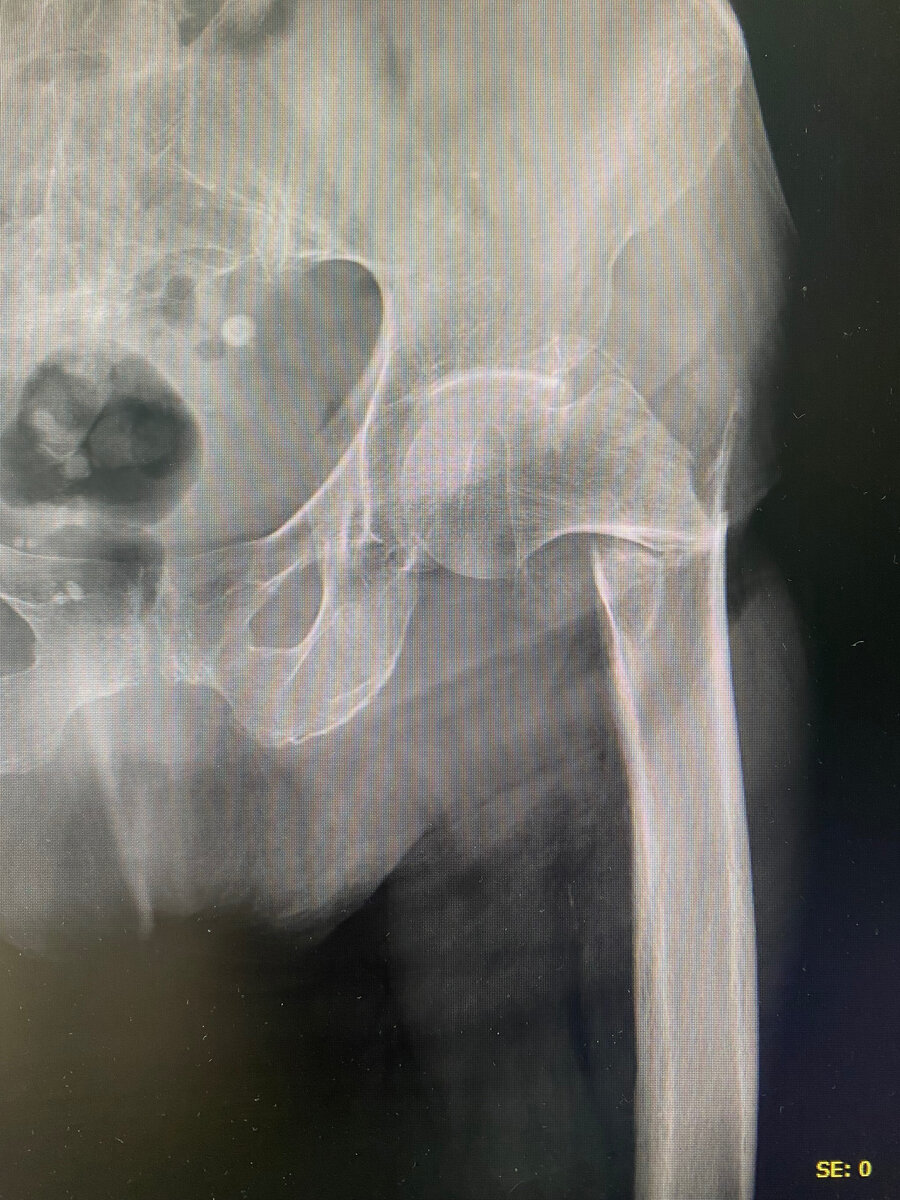

интрамедулярный стержневой остеосинтез бедренной кости у пациентки 82 лет